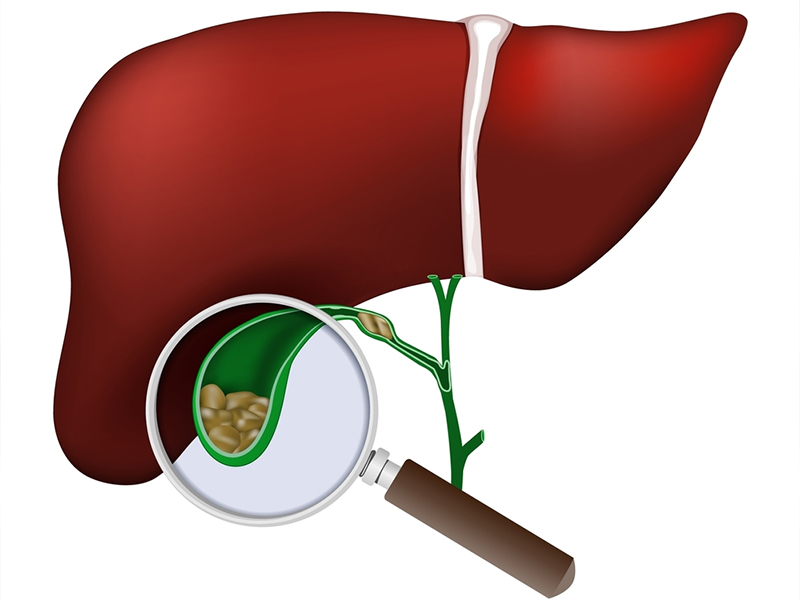

Laparoscopic Gallbladder Stone Surgery

Your gallbladder is a pear-shaped organ that stores bile, the fluid that helps digest food. If it's not working the way it should..